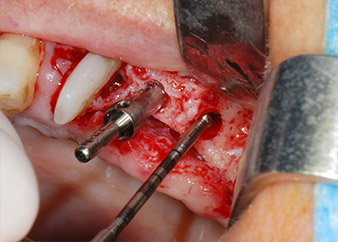

Въпреки това, ние се придържахме към първоначалния си план да запазим и двата зъба като абатмънти за временен мост по време на 6-месечната остеоинтеграция на имплантите. При повторна интервенция, ситуацията трябва да се преразгледа. Първо, в опит да се овладее ендо-перио проблема, останалата повърхност на зъба е внимателно обработена с пиезохирургично оборудване (Piezomed, W&H, използван с накрайник S1 под формата на шпатула, първоначално проектиран за ерозия на латералната синусна стена) (Фиг. 4).

След това апексът се изпилява със същия инструмент, за да се отстрани остатъчната инфектирана апикална тъкан и да се намали възможното допълнително усложнение по кореновите канали (апикоектомия) (Фиг. 5). Ретроградно запълване не е необходимо, защото ортоградното запълване току-що е ревизиран.